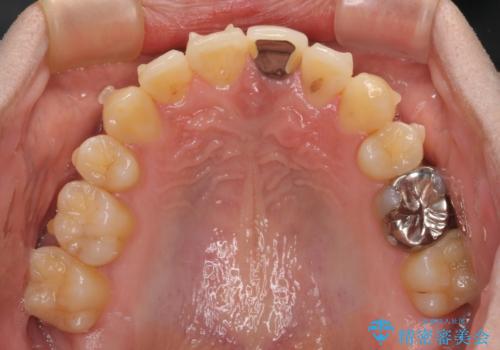

- 下顎の八重歯を気にして来院された患者様です。

左下以外、3本の第一小臼歯が既に抜去されており、左下は八重歯になっている状態でした。

左下の八重歯は手前に傾斜していたため、インビザラインによる抜歯矯正が可能と判断し、後方にある第一小臼歯を抜歯してインビザラインにて矯正治療を行うこととしました。

ワイヤー矯正と比較すると、八重歯が後方に傾斜した仕上がりとなりましたが、患者様ご希望のインビザラインにて十分な歯列を達成することができました。